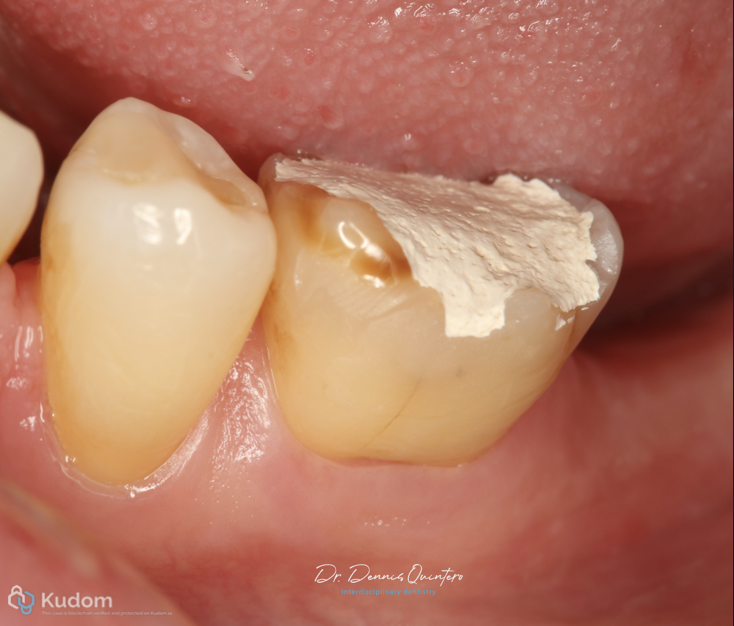

Fig. 2

Initial clinical situation

Fig. 3

. Tooth 3.6 with irreversible pulpitis.

. Occlusal structural loss.

Fig. 4

. Occlusion diagnosis.

. Absence of 3.7.

. Is very important to make the correct restoration to avoid any vertical fracture in the future.